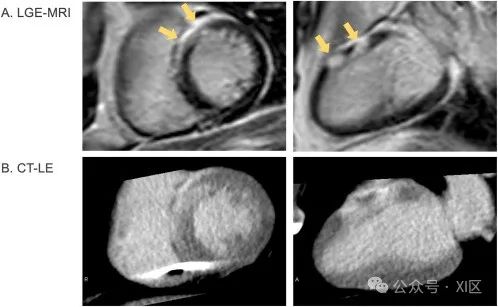

使用起搏器植入前(A)的LGE-MRI和起搏器植入后(B)的CT-LE对一名心脏肉瘤患者的 LE进行评估。LGE-MRI显示心前壁有心外膜LE,CT-LE也能很好地显示这一结果,尽管下壁存在起搏器导联的金属伪影。在特定的临床情况下,CT-LE的额外采集凸显了其实用性。虽然 CT 对于经导管主动脉瓣置换术(TAVR)的术前规划至关重要,但通过CT测量ECV有助于全面评估潜在的心肌病变,尤其是考虑到16%的主动脉瓣狭窄患者可能患有心脏淀粉样变性。CT在评估冠状动脉疾病、肺栓塞和主动脉夹层的 "胸痛三联 "策略中表现出色。在肌钙蛋白阳性的急性胸痛病例中,额外的CT-LE和ECV测量可用于排除心肌炎和冠状动脉非阻塞性心肌梗死(MINOCA)。